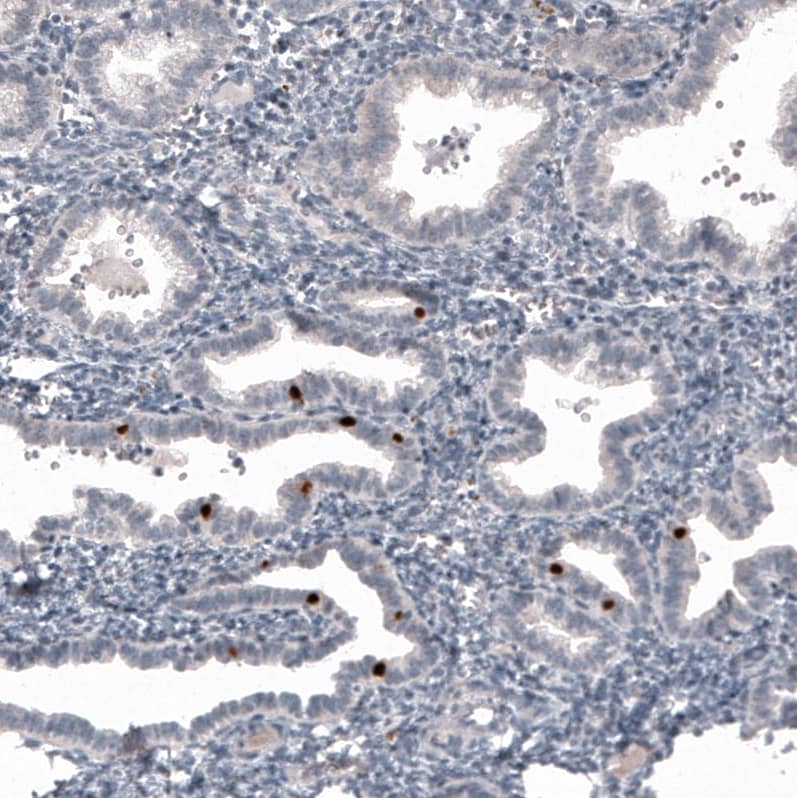

FoxJ1/HFH4 Antibody (CL3991) - Azide and BSA Free Immunohistochemistry-Paraffin: FoxJ1/HFH4 Antibody [NBP3-44121]

Immunohistochemistry-Paraffin: FoxJ1/HFH4 Antibody [NBP3-44121]

Analysis in human fallopian tube and skeletal muscle tissues using NBP3-44121 antibody. Corresponding FoxJ1/HFH4 RNA-seq data are presented for the same tissues.

Staining of human fallopian tube shows moderate to strong nuclear positivity in glandular cells.

Staining of human endometrium shows strong nuclear positivity in a subset of glandular cells.